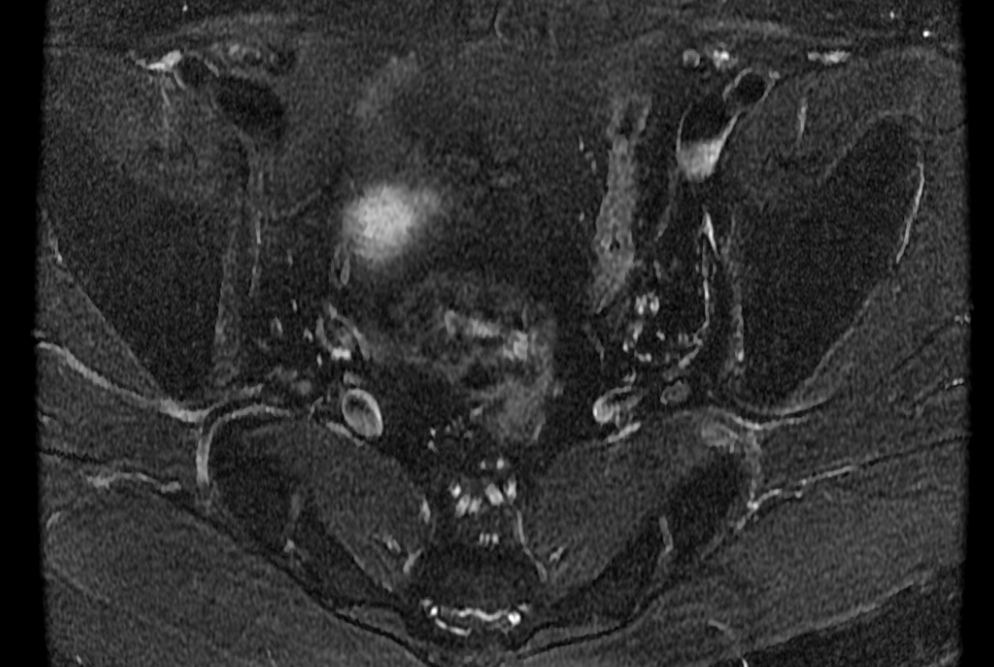

Bilateral accessory piriformis muscles at the S2 level attaching to the sacral body, anterior the S2 nerve roots. Normal piriformis muscles should be posterior to the sacral nerve roots. The result is that the S2 nerve roots may be pinched between the piriformis and accessory piriformis muscles.

Bilateral accessory piriformis muscles